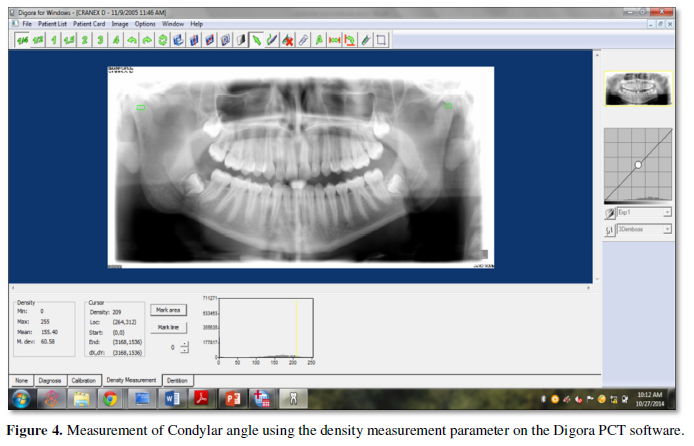

Digital panoramic radiography is used for TMJ screening when the clinical examination suggests some form of joint pathology [1] and also for determining gross bony changes in the condyle [2]. It has also been shown that there is consistency and accuracy with digital radiographs of the condylar area. Also, digital imaging with the aid of recent software systems helps in assessing various morphological changes and other bone density parameters that are not possible to measure using conventional radiographs.

The condylar bone density was measured by marking a square area covering the condyles of both sides and density was measured using the density measurement parameter on the Digora PCT software (Figure 4). For each measure a score of “zero” equated to no demonstrable change,”one” represented mild change, and “two” signified gross change.

The average condylar density in Indian population was in range of 88 to 91mg/cm3. The observed condylar shapes and radiographic bone changes were significant with condylar height. When comparison was done between dentition status and measurements made on condyles shows a statistically significant difference with condylar height asymmetry index and horizontal angles measured on left condyles.